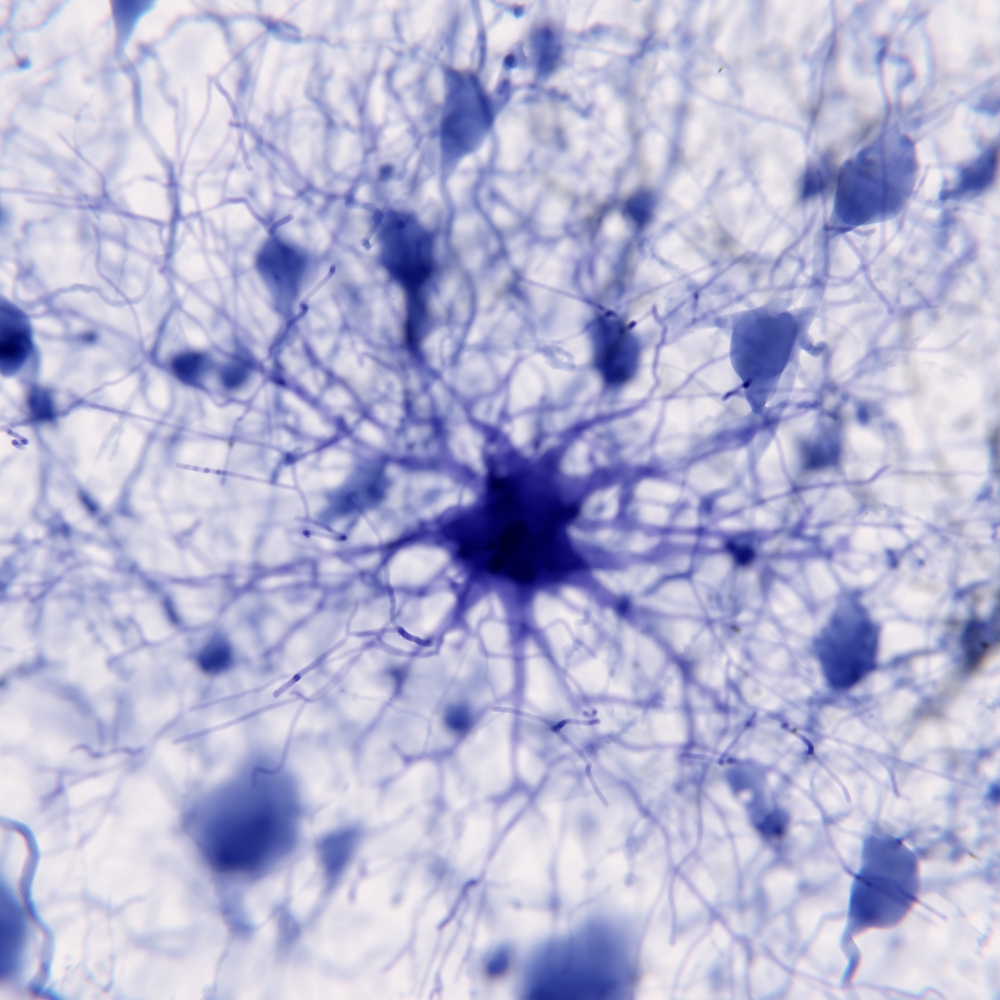

The Role of Astrocytic Mitochondrial Metabolism in Chronic Stress – ASTROMICS